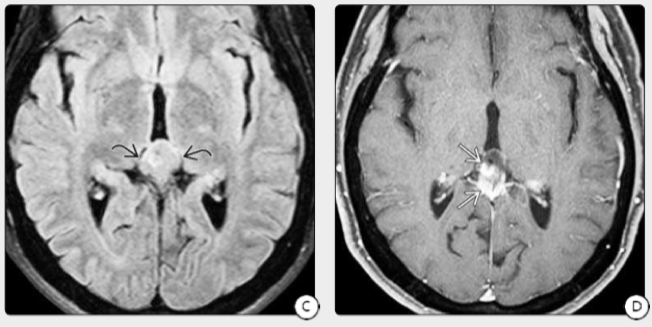

CT检查:CT平扫肿瘤可呈低密度,等高混杂密度或均一稍高密度病灶,肿瘤呈边界清楚的类圆形病灶,可有散在小钙化灶,双侧侧脑室及三脑室前部扩大,有室管膜或室管膜下转移的可见两侧侧脑室及三脑室周围带状略高密度病灶,可呈均匀一致的对比增强。

MRI检查:MRI检查肿瘤在T1加权像呈等信号,也可呈低信号,而在T2加权像为高信号,矢状位扫描有助于了解肿瘤的生长方向以及中脑受压的程度,Gd-DTPA增强对比亦为均一强化表现。